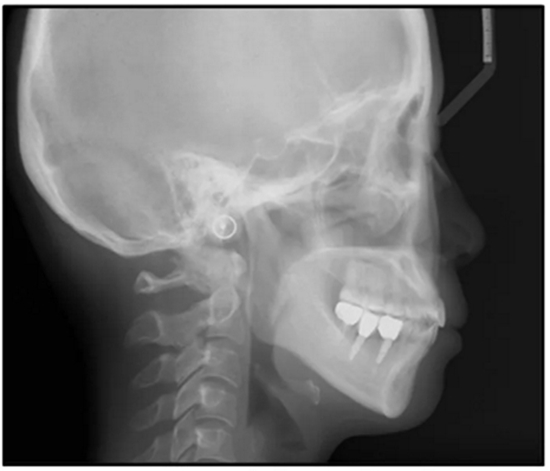

36歲;女性;尋求下頜左后方區(qū)域間隙管理的建議(圖1和圖2),通過治療獲得了良好的牙頜面效果(圖3和圖4)。她被診斷患有骨性I類和代償性牙性II類錯合畸形,并且上頜左側(cè)尖牙缺失(圖1和2)。大約七年前,由于不可修復(fù)的齲齒,拔除了下頜左側(cè)第一和第二磨牙(圖5)。37相鄰的第三磨牙向近中移動并傾斜入間隙,導致無牙頜間隙減小至約14 mm(圖2和圖5)。臨床和影像學評估顯示多發(fā)性齲損和在下頜右側(cè)567處有一不良的固定橋修復(fù)體(圖1和5)。此外,下頜左中切牙缺失,造成下頜中線向左側(cè)偏移約3 mm(圖1和圖2)?;颊咦栽V,她的右上第一前磨牙和左上尖牙在13歲時由其家庭牙醫(yī)拔除,因為它們被阻塞到頰側(cè)萌出(圖1)。上頜第二磨牙缺失(未知病因),并且相鄰的第三磨牙已經(jīng)轉(zhuǎn)移到第二磨牙間隙中。如補充材料所示,美國正畸學差異指數(shù)DI是28分。種植體部位(下頜左側(cè)和右側(cè)第一磨牙)由于復(fù)雜性得到額外4分(補充材料)。

總之,這種復(fù)合錯合畸形是一個很嚴重的問題,需要進行認真的多學科序列治療。治療后X光片(圖6)和重疊頭影測量圖(圖7)記錄了跨學科治療結(jié)果。

圖5. 治療前的側(cè)位片(上圖)和全景(下圖)的X光片